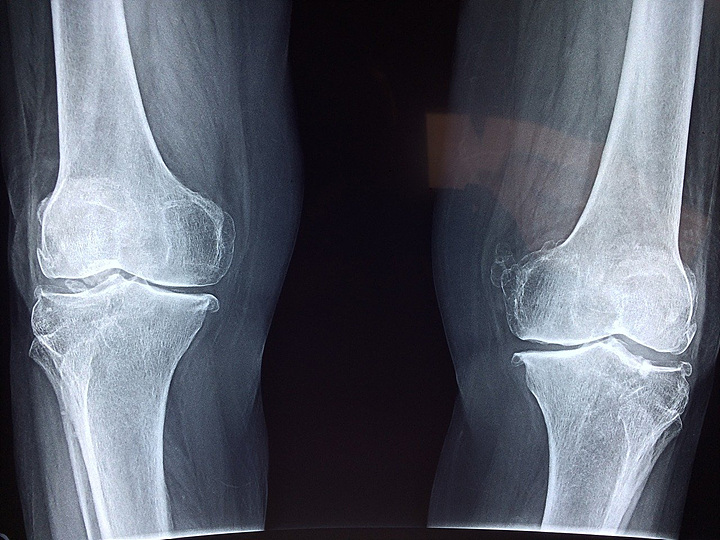

나의 뼈가 튼튼한지 알아보려면 골밀도 검사를 해 보면 알 수 있습니다. 건강검진받으실 때 꼭 골밀도 검사를 함께 받아보시길 권장하며 뼈에 도움 되지 않는 식품의 섭취를 줄여 소중한 뼈 건강 지키시길 바랍니다.